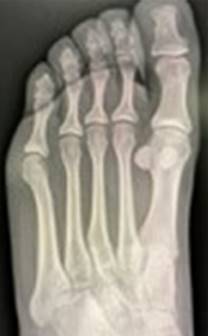

Con previo consentimiento de los padres y la paciente, bajo anestesia local con lidocaína al 2% (3 cm3), se realiza reducción cerrada de la fractura epifisaria mediante tracción del segundo dedo y digitopresión en dirección plantar de la cabeza del metatarsiano. Se toman radiografías de control posterior al procedimiento; se encuentra reducción anatómica de la fractura (Figura 2). Se colocó zapato postquirúrgico por cuatro semanas y se reincorporó a actividades de la vida diaria dos meses posteriores a la fractura. Se realizó seguimiento clínico y radiológico de forma esporádica sin complicaciones en su evolución, se anexa radiografía a 36 meses de evolución (Figura 3).

Figura 3: Radiografía anteroposterior de pie a 36 meses de la fractura. Se observa adecuada reducción y sin complicaciones a largo plazo.